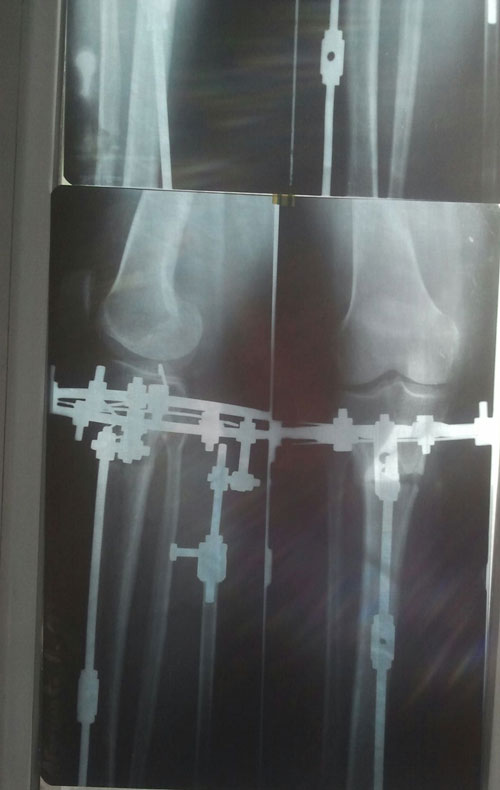

рентген в 120 дней.

Сращение идёт медленно на одной ноге. Ждём ещё месяц.